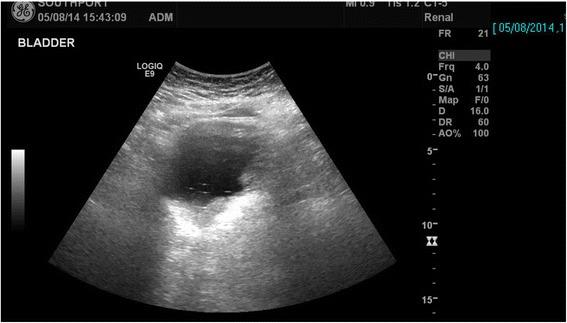

A tetraplegic patient started sweating profusely following insertion of a Foley catheter per urethra. The catheter was draining urine; there was no bypassing, no bleeding per urethra, and no haematuria. Patient's wife, who had been looking after her tetraplegic husband for more than forty years, told the health professionals that the catheter might have been placed incorrectly but her concerns were ignored. Ultrasound scan of urinary tract revealed no urinary calculi, no hydronephrosis. The balloon of Foley catheter was not seen in urinary bladder but this finding was not recognised by radiologist and spinal cord physician. Patient continued to sweat profusely; therefore, CT of pelvis was performed, but there was a delay of ten days. CT revealed the balloon of Foley catheter in the over-stretched prostate-membranous urethra; the tip of catheter was not located within the urinary bladder but was lying distal to bladder neck. Flexible cystoscopy was performed and Foley catheter was inserted into the bladder over a guide wire. The intensity of sweating decreased; noxious stimuli arising from traumatised urethra might take a long while to settle.